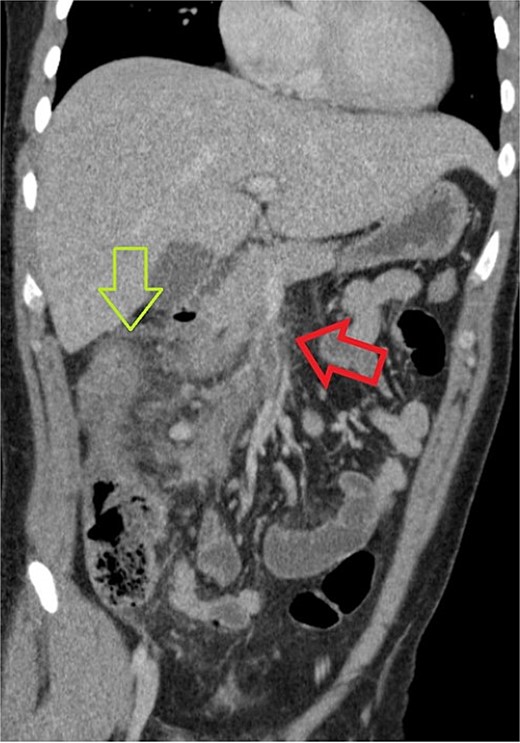

One week later, the patient returned to the emergency department with complaints of severe generalized abdominal pain for several days, fever, and emesis. During this presentation, the patient was noted to be febrile to 38°C and tachycardic. Laboratory studies were obtained and complete blood count was remarkable for a white blood cell count of 22.7 with a left shift. However, lactic acid levels were within normal limits. Upon performing a physical examination, there was diffuse and moderate tenderness to the right side of the abdomen and epigastrium. Given the recent surgery, there was concern for a potential complication. His presentation prompted another CT of the abdomen and pelvis, and this showed a superior mesenteric vein thrombosis with a discontinuous right portal vein thrombosis near the dome of the diaphragm. Additionally, there was notable associated edema of the ascending and transverse colon suggesting colitis secondary to poor venous drainage (Fig. 1). Due to the finding of thromboses, a D-dimer level was obtained and found to be 3.7.

CT of abdomen and pelvis showing a thrombus within the superior mesenteric vein, identified with a red (or horizontal) arrow. Some linear foci which may be branching of hypoattenuation in segment 8 of the liver which possibly related to distal branches of the right portal vein and could represent early portal vein thrombosis. The green (or vertical) arrow identifies colonic edema at the hepatic flexure.